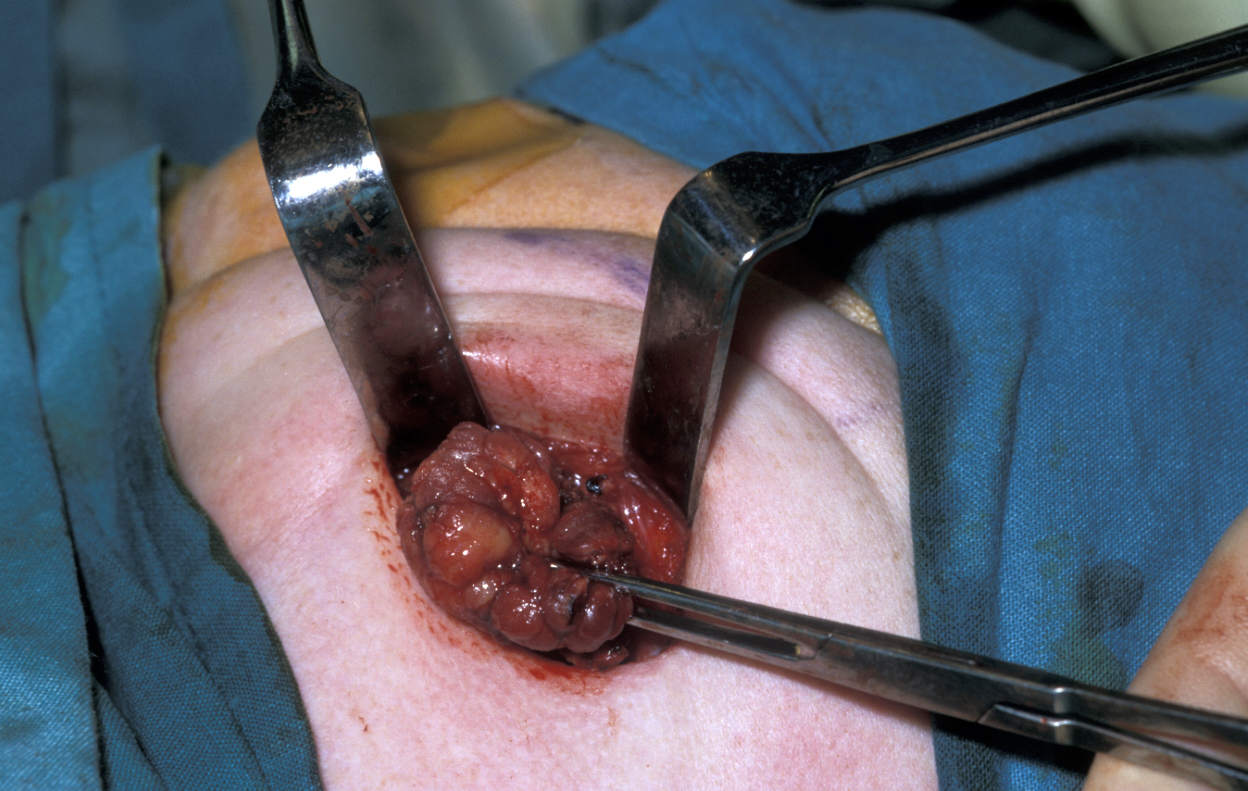

An example of a very common procedure is the excision of mucocele, a type of cyst that is associated with the minor salivary glands.

Figure 1: A mucocele of the lower lip – the most common site. A supposed ‘mucocele’ of the upper lip is usually a tumour.

Similar to the surgical treatment of other cysts, also the surgical treatment of mucocele aims for the complete removal of the cyst. It requires adequate local analgesia, usually via bilateral mental nerve blocks. Excision is then accomplished by performing a mucosal wedge excision that avoids resecting the vermilion border (demarcation between lip and adjacent normal skin). Alternatively, the cyst itself can be dissected out submucosally. Most mucoceles are cured by mucosal wedge incision and removal of the associated damaged minor salivary glands. However, there is a small risk of recurrence.